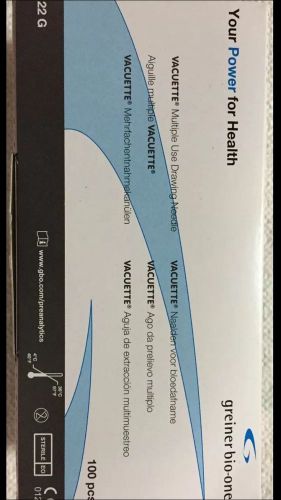

NEW (20 Box X 100) Vacuette 22G x 1-1/2" Blood Collection Needles (2000 Needles)